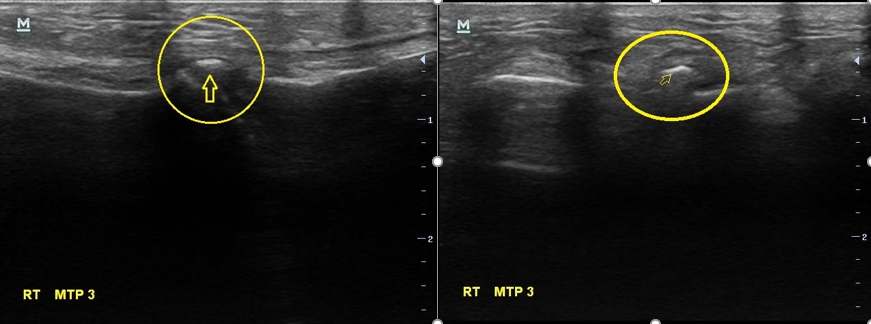

검사상에서는 특별한건 없습니다. 이유없이 발이 아프다는 분들의 경우 평발이나 요족인 경우가 종종 있는데 이 여성분의 발은 평발도 요족도 아닌 상태로 보였습니다. 그래서 초음파 검사를 했습니다. 그 결과는...

나 : X-ray는 괜찮은데요... 초음파에서 문제가 보이네요.

나 : 초음파에서 여기 하얗게 보이는거 있죠?

나 : 이건 둘 중 하나인데요.... 첫번째는 금이 갔던 흔적인데.... 다친적은 없다고 하셨으니... 제 생각엔 석회 조각인거 같네요

나 : 네 석회성 건염이라고 해서 관절이나 힘줄 부위에 석회 조각이 생기고 이게 갑자기 염증을 만드는 경우가 가끔 있습니다.

이 여성의 병명은 '석회성 건염'이었습니다. 석회성 건염이라는 것은 우리 몸 관절부위에 석회가 쌓이면서 덩어리를 만들고 이게 염증을 만들어서 통증이 발생하는 병을 말합니다.